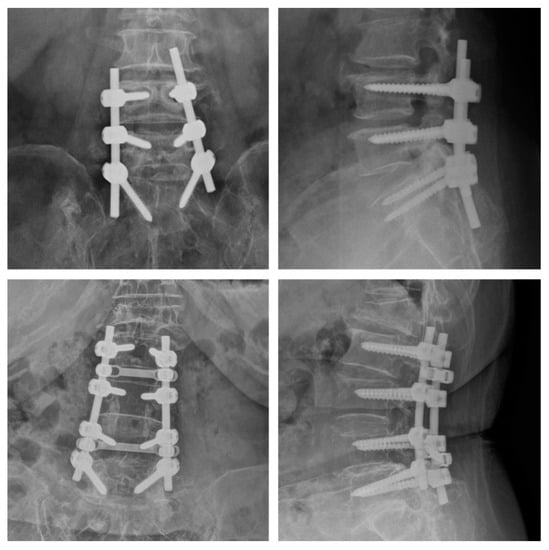

Treatments for spondylolisthesis include selective nerve blocks, which are aimed at reducing back pain, and posterior spinal fusion treatments that help stabilize the spinal structure, as shown in Figure 12.

Figure 12.

Posterior spinal fusion.